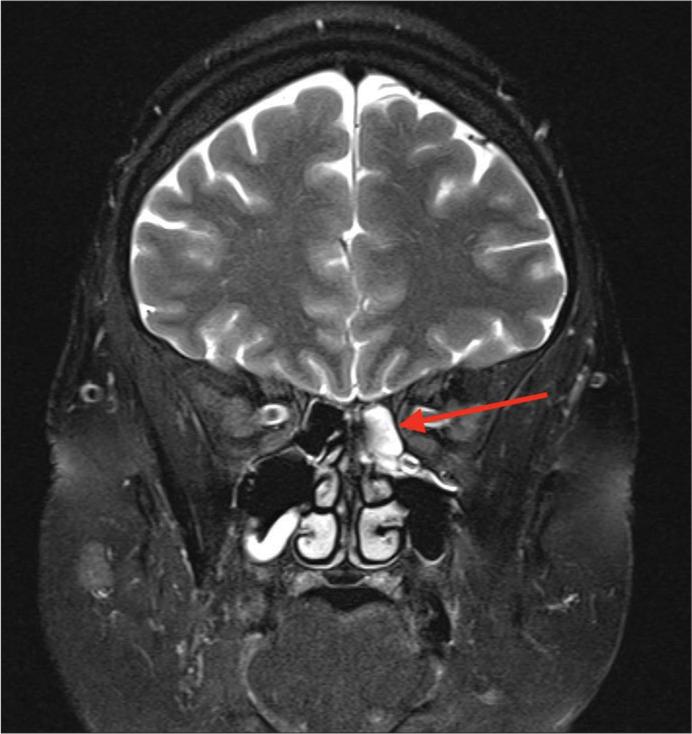

A 54-year-old patient presented with a 9-month history of cerebrospinal fluid (CSF) rhinorrhea and headache on a background of antiphospholipid syndrome. Investigations showed a superior vena cava (SVC) and right internal jugular vein (IJV) obstruction with moderately elevated intracranial venous pressures. Her magnetic resonance imaging (MRI) brain was consistent with a CSF leak. The patient underwent successful endovascular stenting of her obstructed SVC and right IJV followed by surgical repair of a herniating meningocele in the posterior left ethmoid air cells.

一名54岁患者,有抗磷脂综合征病史,出现脑脊液鼻漏和头痛9个月。检查显示上腔静脉(SVC)和右颈内静脉(IJV)阻塞,颅内静脉压中度升高。她的脑部磁共振成像(MRI)与脑脊液漏相符。患者成功接受了阻塞的SVC和右IJV的血管内支架置入术,随后对左侧后筛窦气房的脑膜膨出进行了手术修复。